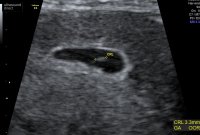

New tests and digi added

Lovely to see your scan pictures tdog. So glad it all went well for you, bet you feel relieved and happy now

Wonderful!!! Also, I just want to say, yup, knew it was a singletonsorry I couldn't resist. I'm so happy it went well dear.

Yay! Congrats! So beautiful!

Beautiful..did you hear heartbeat yet?

No lovely they didnt put it on screen but showed us the flickering

Love the scan aw so exciting. I’m not sure how I’ll not book a private early scan before the 12 week one! X